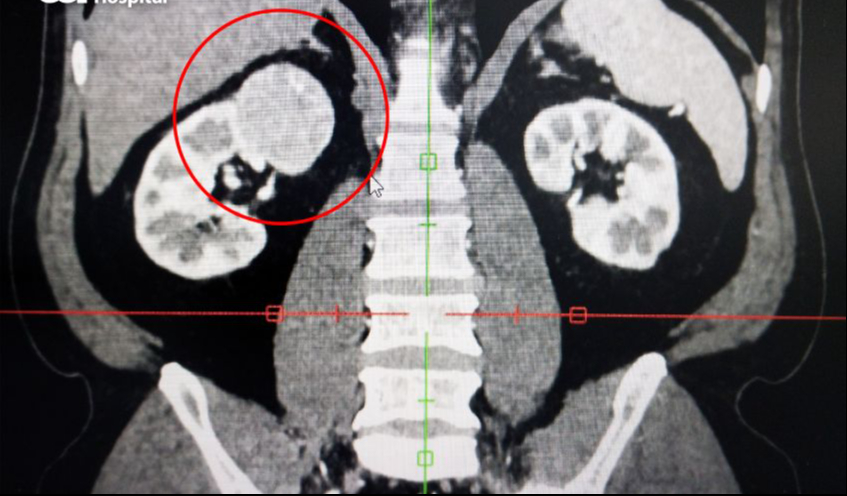

Theo thông tin từ BVĐK Tâm Anh, Ths, Bs Nguyễn Tân Cương, Phó khoa Tiết niệu, Trung tâm Tiết niệu – Thận học – Nam khoa cho biết, qua ảnh chụp cắt lớp vi tính (CT-scanner) nhận thấy khối u thận phải có kích thước 4,5×5,0 cm, ở cực trên thận phải, đậm độ không đồng nhất, u nằm sát tĩnh mạch thận phải (mạch máu đưa máu từ thận về tim), gần tĩnh mạch chủ bụng, ngay bên dưới gan, gần tá tràng (phần ruột non nối với dạ dày) và đại tràng.

Ảnh chụp CT cho thấy khối u thận phải (khoanh đỏ) của ông D. nằm ở vị trí phức tạp, gần nhiều cơ quan xung quanh. Ảnh: BVCC